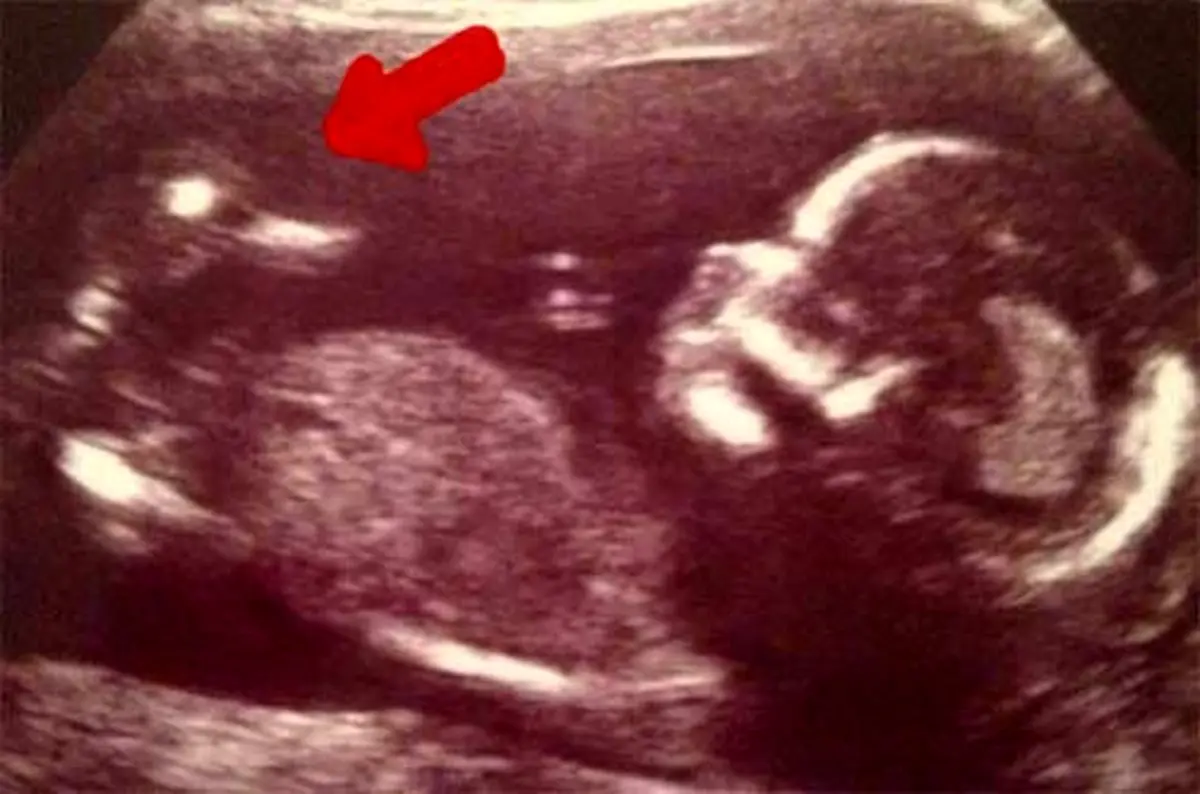

این زن به همراه نوزادش ، یک اردک را نیز باردار است ! باز تصاویر سونوگرافی یک زن اردکی را کنار جنین در رحم مادر نشان داد که سبب تعجبب متخصصان شد . همیشه زنان باردار در زمان مراجعه با سونوگرافی مشتاقند بدانند نوزادشان دختر است یا پسر ، سالم است یا نه و اینکه چه شکلی است .

اما این زن باردار با دیدن نتیجه سونوگرافیش شوکه شد. وی بزرگترین شوک زندگی خود را زمانی تجربه کرد که برای سونوگرافی به پزشک Doctor مراجعه کرده‌ بود اما تصویر نوزاد به دنیا نیامده‌اش تنها چیزی نبود که او روی صفحه مانیتور دید.یک اردک در کنار کودکش این زن باردار و پزشکش را شوکه کرد.

این زن جوان بعد از سه سقط جنین برای بار چهارم مجدد باردار شده بود. کورتنی فنویک 28 ساله اهل نیوکاسل در زمان دیدن سونوگرافیش شوکه شد .او بعد از 3 سال مشکل بارداری و 3 بار آی وی اف که با مشکل مواجه شده بود، دوباره باردار شد. این بارداری با توجه به اینکه مادر دچار دیابت Diabetes شد بسیار سخت بود. اما حضور این اردک اسباب خنده آنها را فراهم کرد.

وجود این اردک تنها این والدین بلکه دکتران دیگر را هم شگفت‌زده کرده بود وآن‌ها می‌گفتند تاکنون نه چنین چیزی دیده‌اند نه شنیده‌اند.اکنون این نوزاد به دنیا آمده و در کمال صحت و سلامت به سر می‌برد. هنگام زایمان خبری از اردک فوقالذکر نبود. اما دوستان به یاد آن اردک برای نوزاد به دنیا امده عروسک اردک آوردند. پزشکان هم نتوانستند توجیه مناسبی برای حضور اردک پیدا کنند.